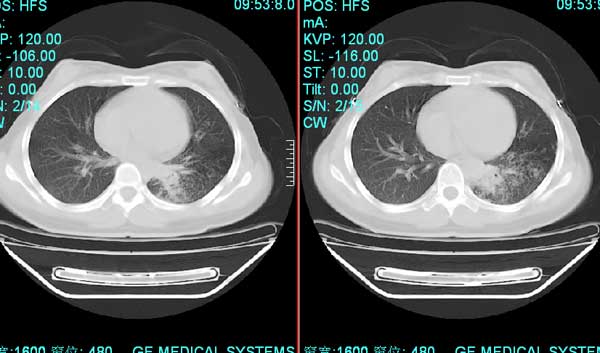

以下是引用pujunzhi在2008-7-1 20:03:00的发言:[br]支持楼主意见!两肺继发性肺结核伴多发空洞形成。